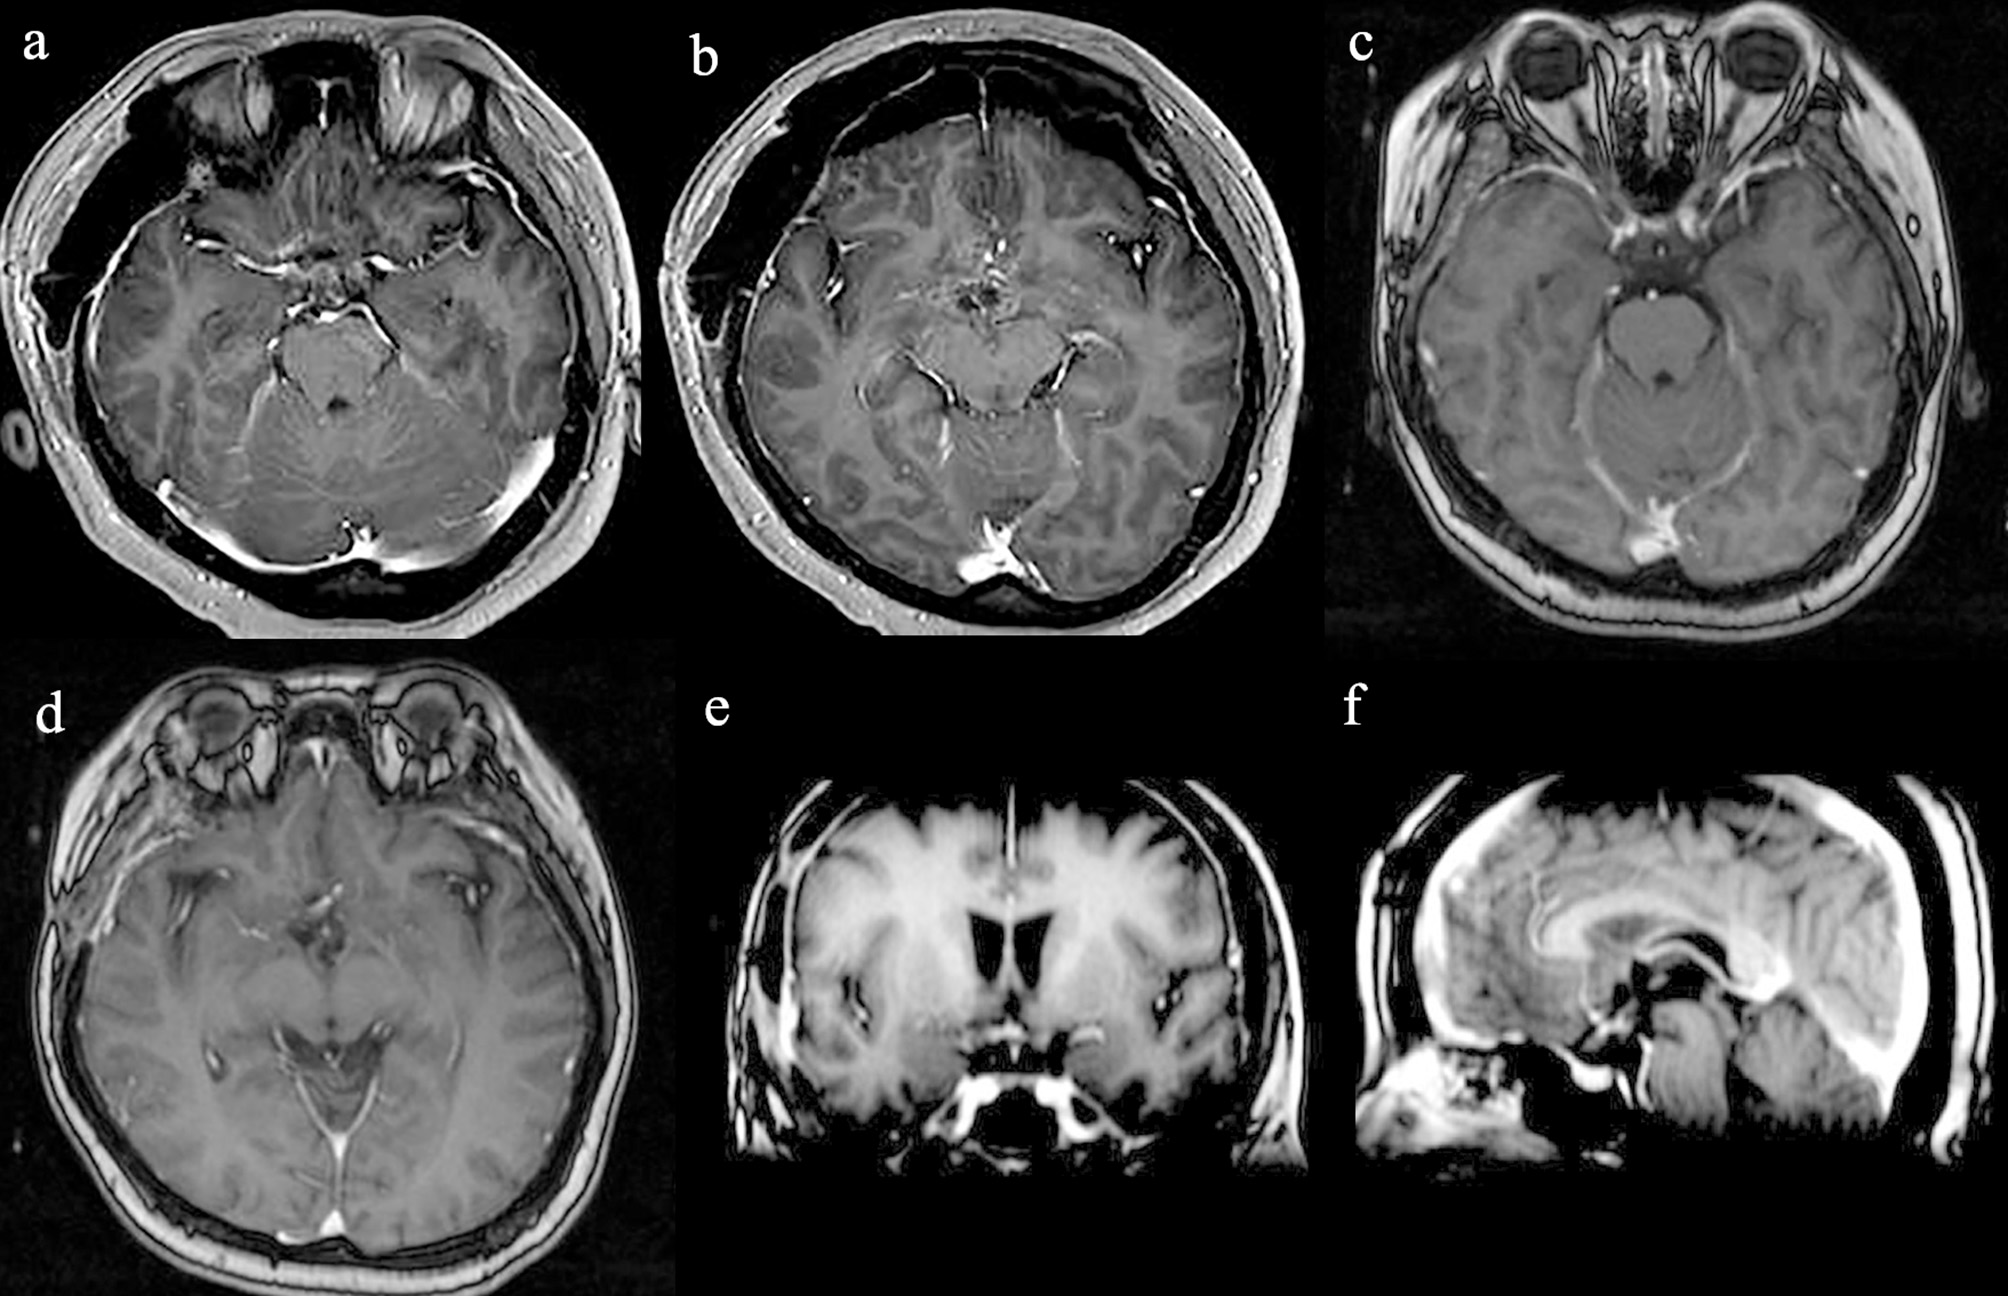

The patient recovered well after surgery. However, she developed postoperative electrolyte disturbance with alternating diabetes insipidus and syndrome of inappropriate antidiuretic hormone secretion. There were no endocrine defects apart from decreased cortisol and ACTH levels in the plasma (Table 1). After 20 days, the electrolyte imbalance subsided. However, MRI 1 month postoperatively showed residual tumor under the third ventricle measuring 1.07 × 0.81 × 0.78 cm (Figures 3a,b). Adjuvant GKRS of the residual tumor with a dose of 15 Gy was advocated by the multidisciplinary team in our hospital on March 22, 2016. The size of the residual tumor decreased following radiosurgery (Figures 3c–f). During 30 months of follow-up, the tumor did not recur, and the patient suffered no complications.

Figure 3

Radiological evaluation of CG postoperatively. Post-contrast MRI images of the residual tumor 1 month (a,b). The size of the residual tumor decreased following GKRS (c–f).

Although CGs are adherent to the adjacent structures, they do not invade the parenchyma. Despite being a low-grade tumor, the prognosis is usually poor because of the location in the deep structure of the brain and the difficulty in performing GTR without causing severe complications (9, 13, 19). However, partial resection of the tumor is associated with high recurrence rates (9, 19, 20). GTR has been shown to be associated with longer recurrence-free survival and better quality of life than STR, although some studies have found that mortality and morbidity rates are much higher following GTR (29 and 67%, respectively) than STR (14 and 50%, respectively) (9, 20, 21). Better tumor control would be achieved with more aggressive resection, but early surgical complications might unavoidably negate the benefit of a more aggressive approach (9). STR was performed in our case via the right modified transpterional port approach, which allowed an adequate exposure of the tumor region with a less invasive parenchymal approach (7). The operation was successful without serious complications. A transient electrolyte disorder occurred postoperatively, which improved after treatment. Adjuvant Gamma Knife radiosurgery (GKRS) of the residual tumor was then advocated. There is no current standard for radiography treatment for CG as there are few such reported cases. GKRS was first used for a residual tumor after STR in 1999, but the radiation dose and outcome were not described (14). In subsequent studies, the radiation dose varied from a marginal dose of 10.5–11 Gy to a maximal dose of 21–22 Gy, which was able to stop tumor progression (9, 10, 18–20). Referring to the previous literature (9, 10, 20), we chose a radiation dose of 15 Gy. There were no postoperative radiotherapy complications, and the size of the residual tumor decreased following radiosurgery. During the 30-months follow-up, the tumor did not recur. With the experience of this case, we propose that in patients in whom GTR is estimated to be too risky, planned STR followed by GKRS with a proper marginal dose could be a safe, effective, and minimally invasive treatment strategy for CG. We recommend that GKRS could be commenced with a low radiation dose of 10 Gy, gradually increasing the dose to 15 Gy and further to 20 Gy if the tumors don't shrink significantly. Further data is necessary to determine the optimal modality and dose of radiotherapy in the treatment of these rare tumors.